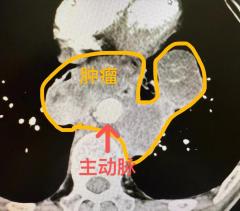

早高峰车祸重伤 西安国际医学中心医院多学科接力上演生死时速